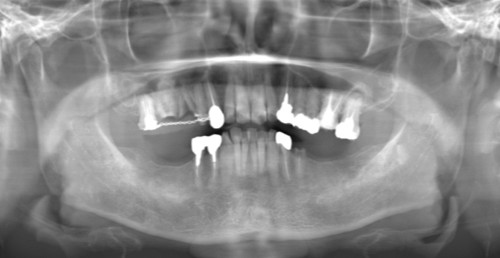

症例1

Before

After

主訴 | 奥歯で噛めるようになりたい |

|---|---|

治療内容 | 下顎の複数本の奥歯をインプラントにて再建 |

治療期間 | 6ヵ月 |

費用 | 200万円 |

副作用・リスク | ・術後に患部に腫れや痛み、違和感などが生じることがあります。 |